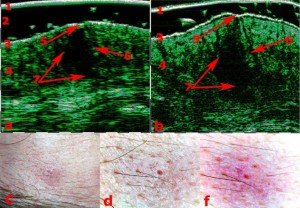

-Διαφοροποίηση μεταξύ υπερτροφικών και χηλοειδών ουλών

-Διάγνωση μορφών ακμής